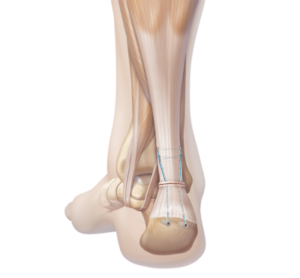

Operative Therapie

Bei einem kompletten Riss mit grossem Abstand der Sehnenenden und aktiven Patienten sollte eine operative Naht der Achillessehne erfolgen. Hierbei werden die Sehnenenden wieder miteinander vernäht und das Gleitgewebe verschlossen.Ob bei Ihnen eine Operation sinnvoll oder gar unumgänglich ist, besprechen wir individuell mit Ihnen.

Nachbehandlung

Nach dem operativen Verfahren bedarf es der Ruhigstellung in einem speziellen Schuh für mindestens 6 Wochen. Je nach Sehnenqualität wird mit dem anschliessenden Aufbauprogramm begonnen. Da Sehnen kaum durchblutet sind, ist die Heilung dementsprechend langwierig. Eine Rückkehr zur vollen Belastungsfähigkeit und somit auch in den Sport kann Monate dauern.